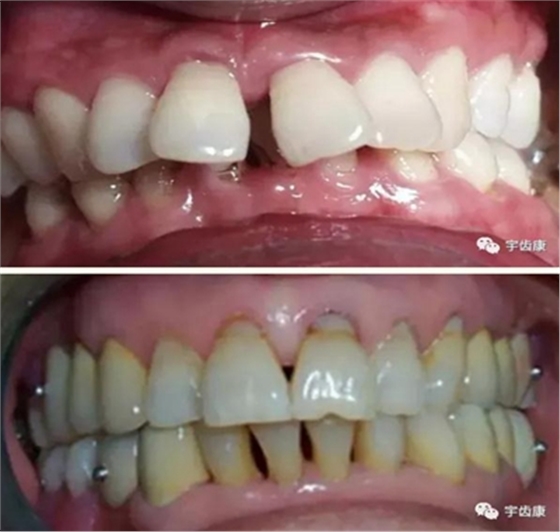

6. 保護(hù)牙周組織

7. 共同就位道的調(diào)節(jié)

模型檢查

模擬預(yù)備